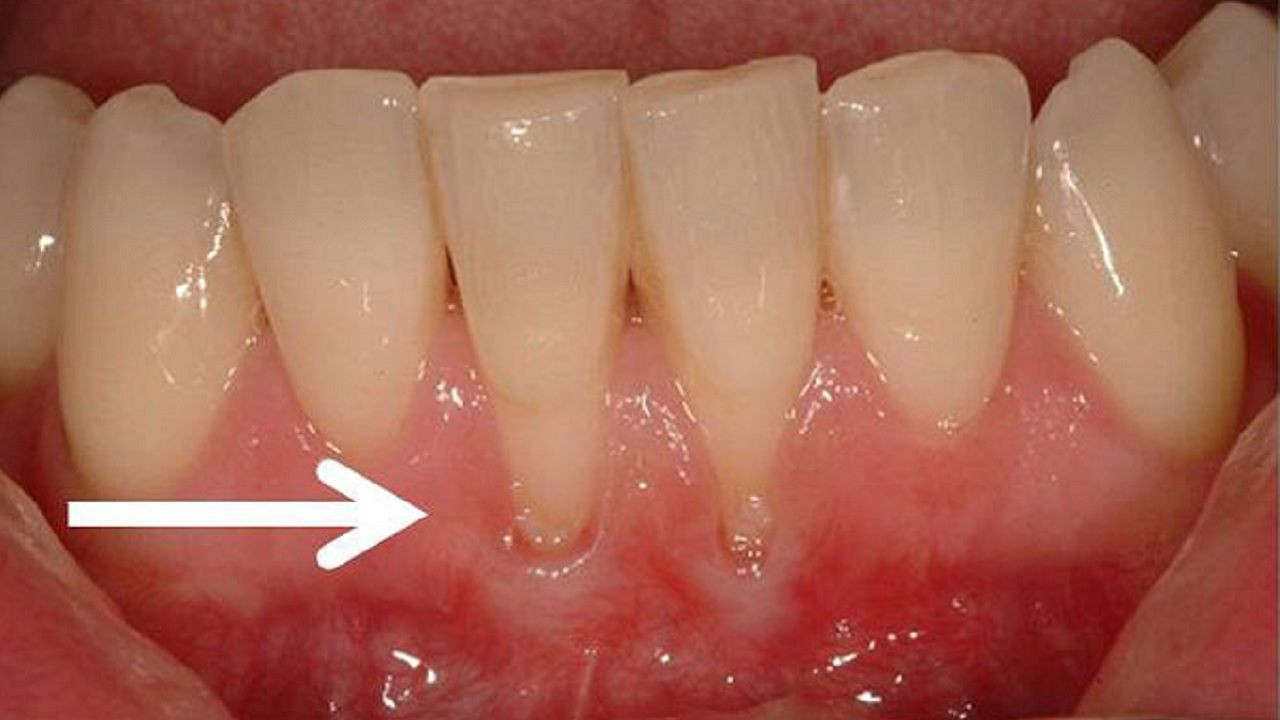

Özellikle diş etlerinde kanama, diş eti çekilmesi ve yemek yerken hissedilen hassasiyet gibi belirtilerin diş eti hastalıklarının habercisi olabileceğini belirten Aydoğan, bu tür şikayetleri olanların vakit kaybetmeden bir diş hekimine başvurması gerektiğinin altını çizdi.